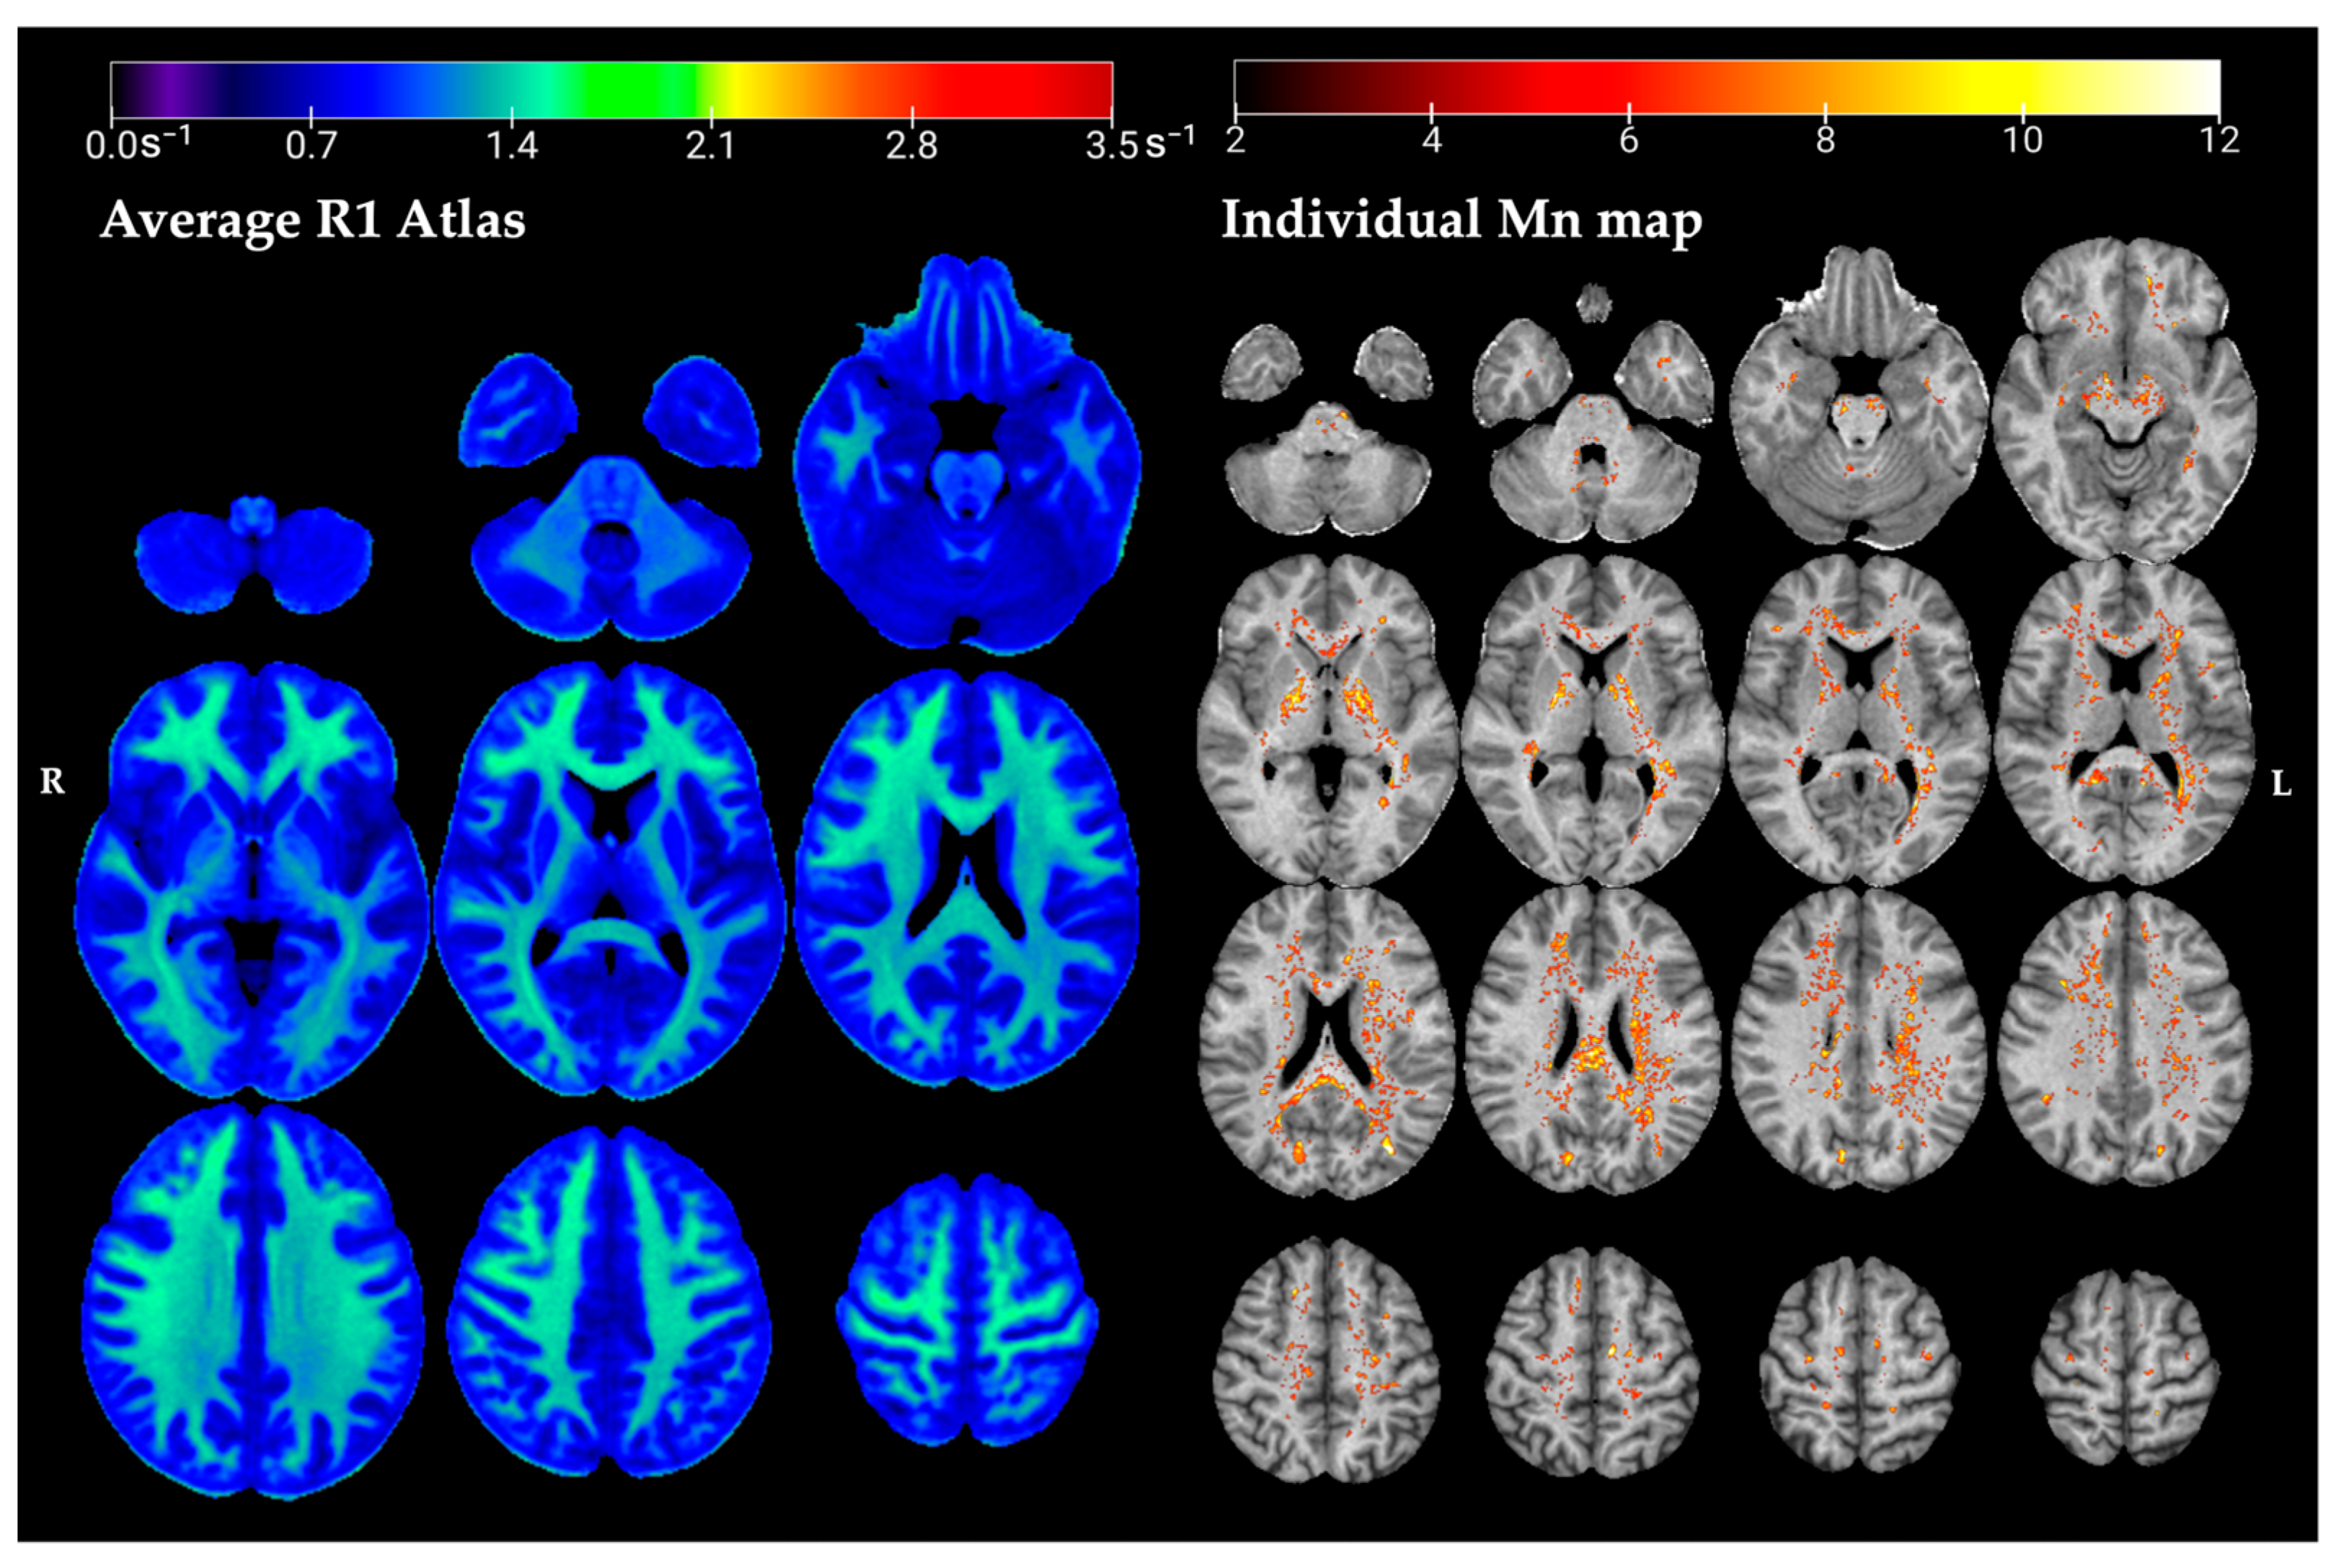

The axial slices of the normative R1 map and an example individual Mn map are presented in Figure 2. The average R1 map corresponds to the intercept coefficient β of E R 1 r = β 0 , R 1 r + β a g e , R 1 r · a g e + β a g e 2 , R 1 r · a g e 2 for the healthy control group (HC) at their mean age of 39 years. At the mean age of 39, the expected R1 in a voxel of the white matter (WM) in the frontal lobe was E{R1} ± RMSE = 1.07 ± 0.15 s−1, and 1.10 ± 0.09 s−1 in the GP.

Figure 2. Axial slices of the normative R1 atlas (left panel). These spatial maps of the intercept coefficients correspond to the average R1 at the mean age of the HC (39 years). The z-scores map is overlayed onto the R1 map of an individual welder (right panel), representing areas of excess Mn accumulation in this individual’s brain.